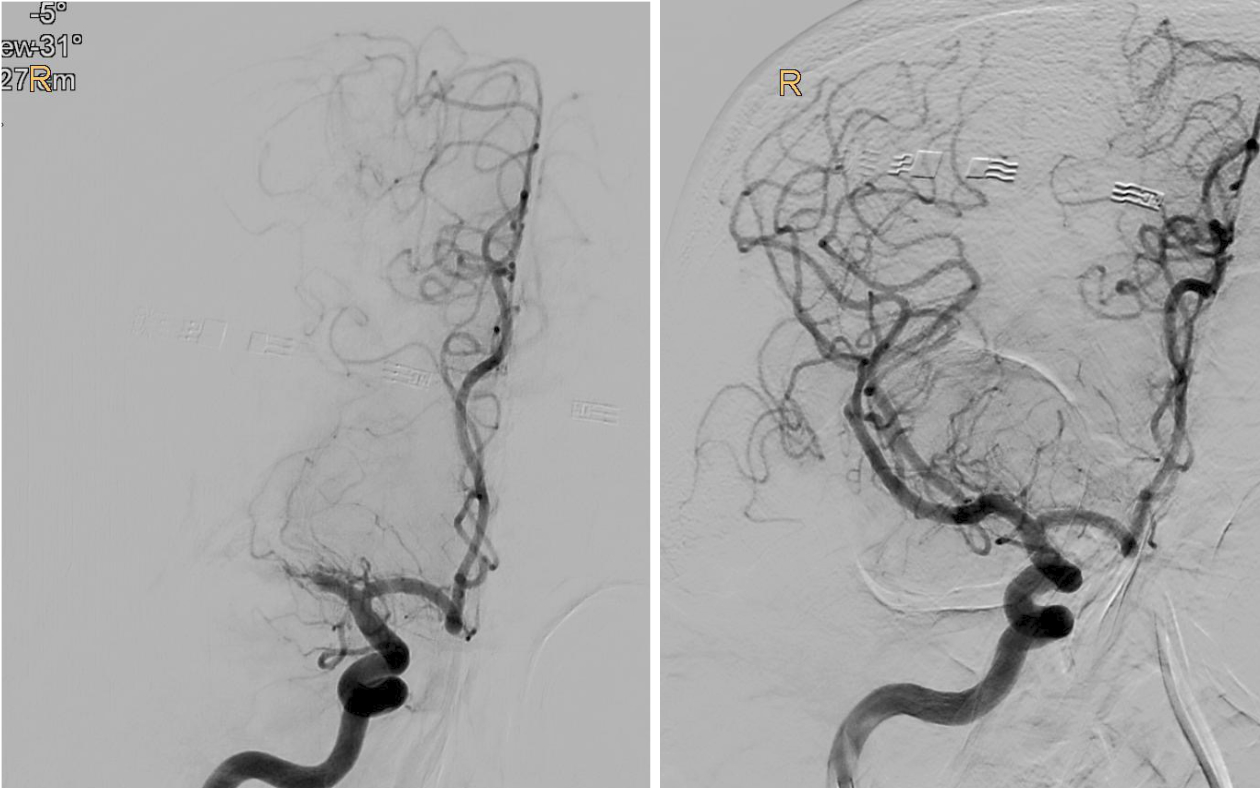

BU: Verschluss des mittleren Hirngefäßes in der Angiographie dargestellt (l.), und wieder eröffnet (r.). Bilder: Univ.-Klinik für Radiologie

„Bei einem Schlaganfall zählen einerseits Zeit und andererseits die noch verbliebene Sauerstoffversorgung des Gehirns, welche bei den PatientInnen unterschiedlich ausfällt. So genannte Kollaterale, Gefäß-Querverbindungen, können die Durchblutung noch einige Zeit aufrechterhalten. Je weniger solcher Kollateralen vorhanden sind, desto weniger Zeit hat man. Doch auch wenn schon Gewebe untergegangen ist, kann man noch etwas retten, wenn man thrombektomiert. Das konnten wir jetzt mit der TENSION-Studie zeigen“, berichtet Gizewski. Viele der PatientInnen könnten trotz der bedrohlichen Ausgangssituation jetzt wieder ein eigenständiges Leben führen. Nachdem sich der Erfolg der Katheter-Behandlung (insgesamt 125 PatientInnen) in der randomisierten Studie im Vergleich zur besten konservativen medizinischen Behandlung (128 PatientInnen) schnell gezeigt hatte, wurde die Studie frühzeitig beendet.